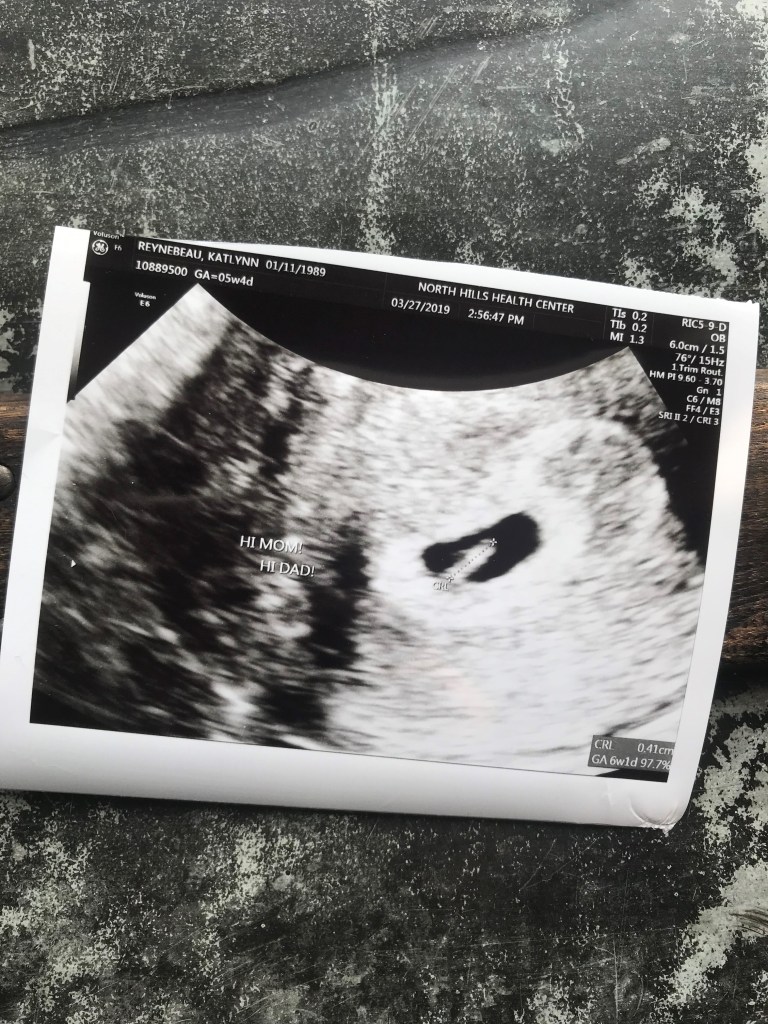

On March 14, 2019 while at work, I found out I was pregnant. After taking a blood pregnancy test in the morning, a nurse called me to confirm the news. We re-tested on March 16, to ensure the pregnancy was developing (which he was). Then on March 27, we had our first ultrasound, he was 6 weeks along and we got to see his heartbeat flickering on the screen.

This truly brought tears to my eyes after three and a half years, we were officially going to be parents.